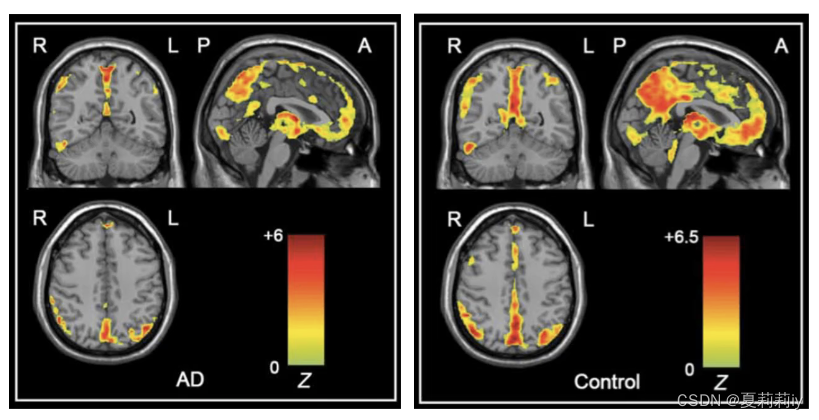

(3)One-Sample T-Test

①可以看看患者和普通人ALFF的图像差异

②在左边栏加入被试,右边是协变量,可以不添加

③生成的结果示例